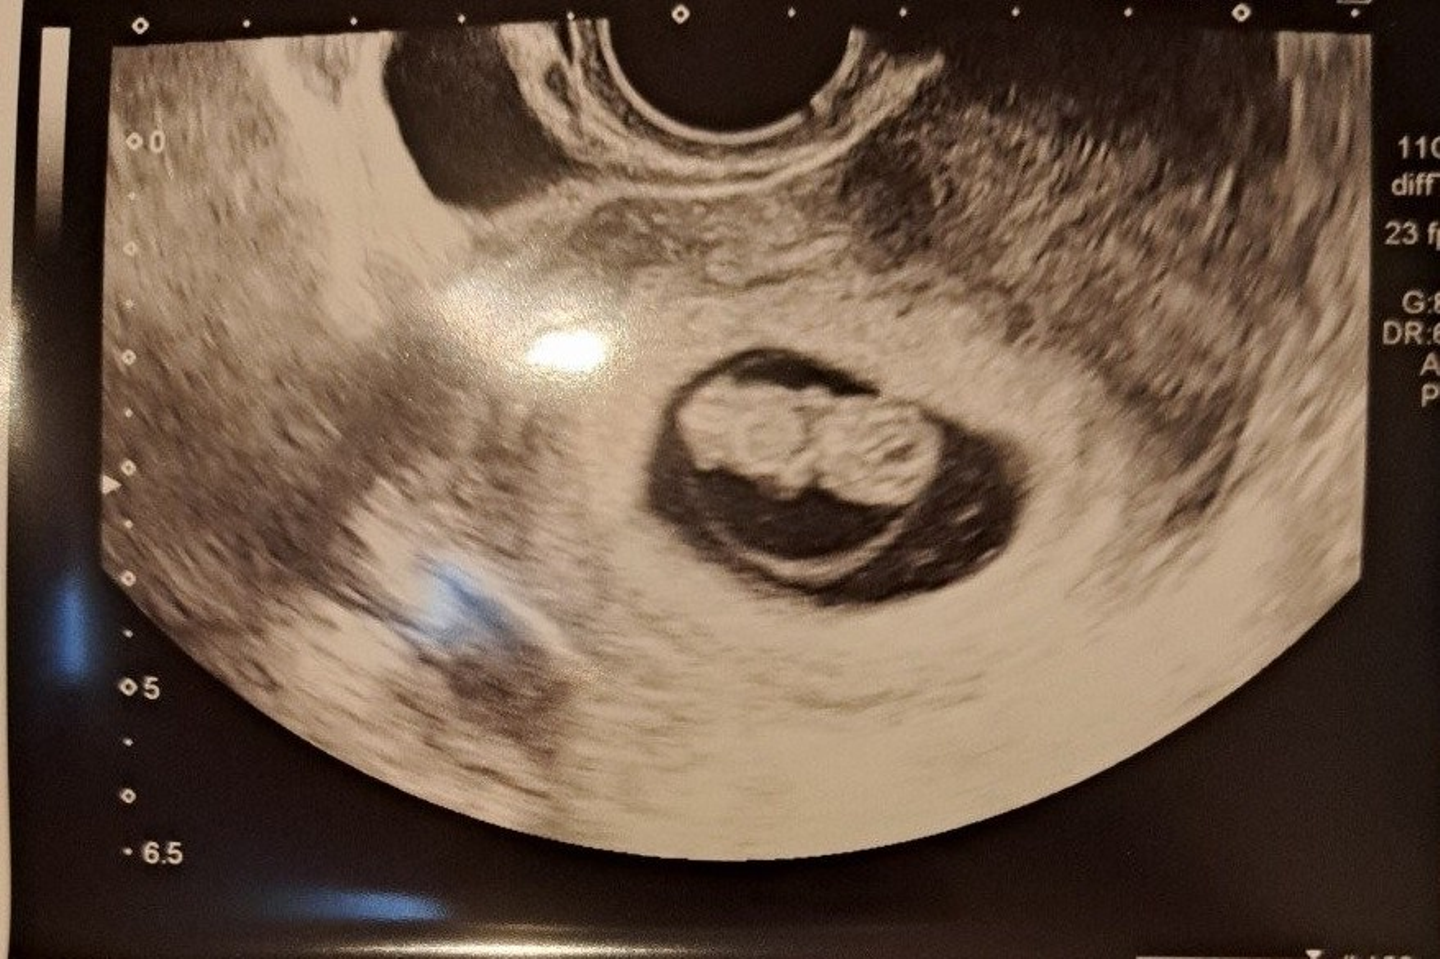

休日も休まずアルバイトをしていたある日のこと、妻から急ぎの連絡が入りました。「何事か」と慌てて帰宅した私を待っていたのは、妻の妊娠の報告でした。

全く予想だにしていなかった展開に、私は1分ほど呆然と立ち尽くしてしまいました。妻は「もっと手放しで喜んでくれると思ったのに」と少し寂しそうにしていましたが、私にとっては、それほどまでに「一人の命を背負う」という責任の重さを実感した、衝撃の瞬間だったのです。